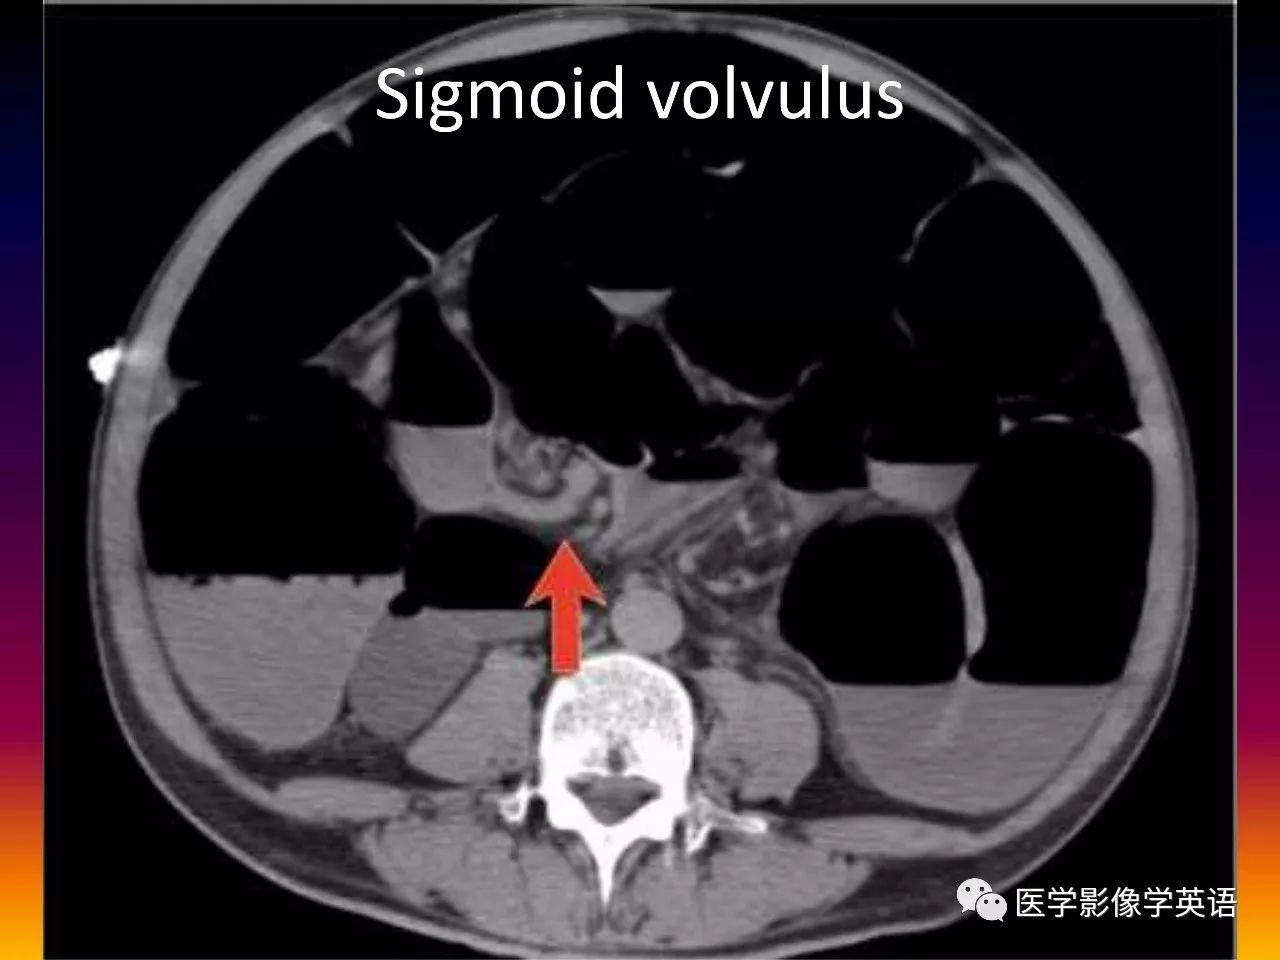

86. Sigmoid volvulus

87. Sigmoid volvulus

45. Volvulus Gastric volvulus Organo-axial Greater curvature above lesser curvature Mesentero-axial Gastric antrum above gastric fundus Midgut volvulus Malrotation (SMV to the left of SMA) Whirl sign Colonic volvulus Sigmoid Whirl sign Cecal Whirl sign